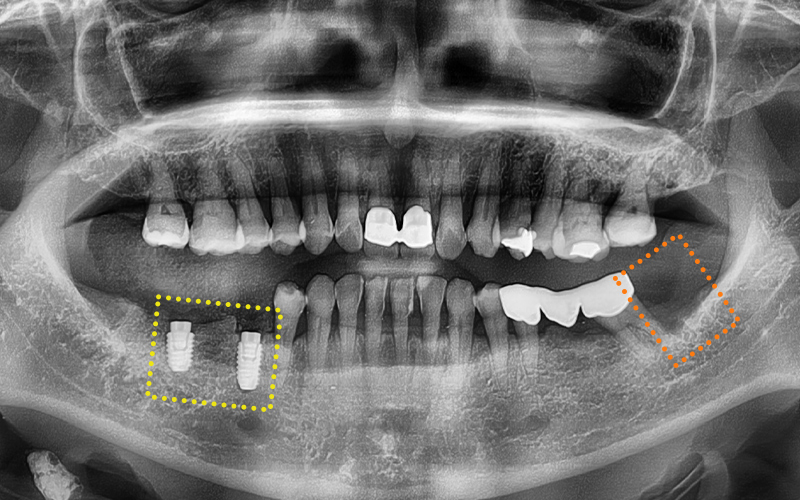

She was experiencing pain in the lower molars on both sides,

and we took a panoramic X-ray

to check the situation in detail.

🦷 Summary of the condition at the time of the visit

✔ The first lower molar on the right

had already been extracted

✔ The second lower molar on the right

was judged to be difficult to preserve due to tooth fracture,

so extraction was decided

✔ The second premolar had a crown already in place,

and it was part of a bridge connected

to the second lower molar

✔ The lower left wisdom tooth

needed extraction due to inflammation